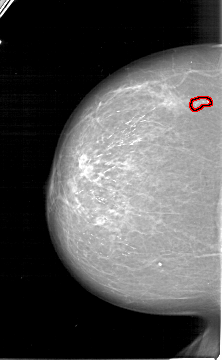

A_1276_1.RIGHT_CC

RIGHT_CC LINES 5461 PIXELS_PER_LINE 3106 BITS_PER_PIXEL 12 RESOLUTION 43.5 NON_OVERLAY